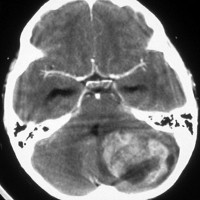

- CTでは小脳より白っぽい灰色(高密度)に写ります

典型的な小脳虫部(小脳の真ん中)の髄芽腫です。横の方,ルシュカ孔へ伸びていないので上衣腫と区別できます。ガドリニウムという造影剤で白く写っています。

この例は,小脳半球にできたものです。のう胞(水たまり)を形成しています。髄芽腫の大きな特徴は,造影剤を入れないCT(左側)で腫瘍が少し白く見えることです(灰白質より高密度といいます)。細胞密度が高いので高密度になります。この例はclassic medulloblastomaですが,MIB-1は45%に達するもので,急激な腫瘍発育を示します。

単純CTでは,腫瘍は比較的境界明瞭で石灰化も高頻度に認められます。充実性腫瘍であることが多いのですが,のう胞あるいは壊死形成も見られます。細胞密度が高い腫瘍であるのでCT等吸収域もしくは高吸収域として描出され,造影剤では均一に強く増強されます。MRIでは,T1強調画像で低信号域として描出され,T2強調画像で等信号から高信号を呈すします。ガドリニウム増強効果は症例により様々であり,強い均一な増強効果を示す例から,ほとんど増強されない症例まであります。髄液播種の頻度が高いので,全脳脊髄にわたるMRI検査が必須です。また,MRIで髄腔転移が認められなくとも髄液細胞診で陽性となることがあるので,もしできれば腰椎穿刺あるいは脳室内髄液によって細胞診を行います。